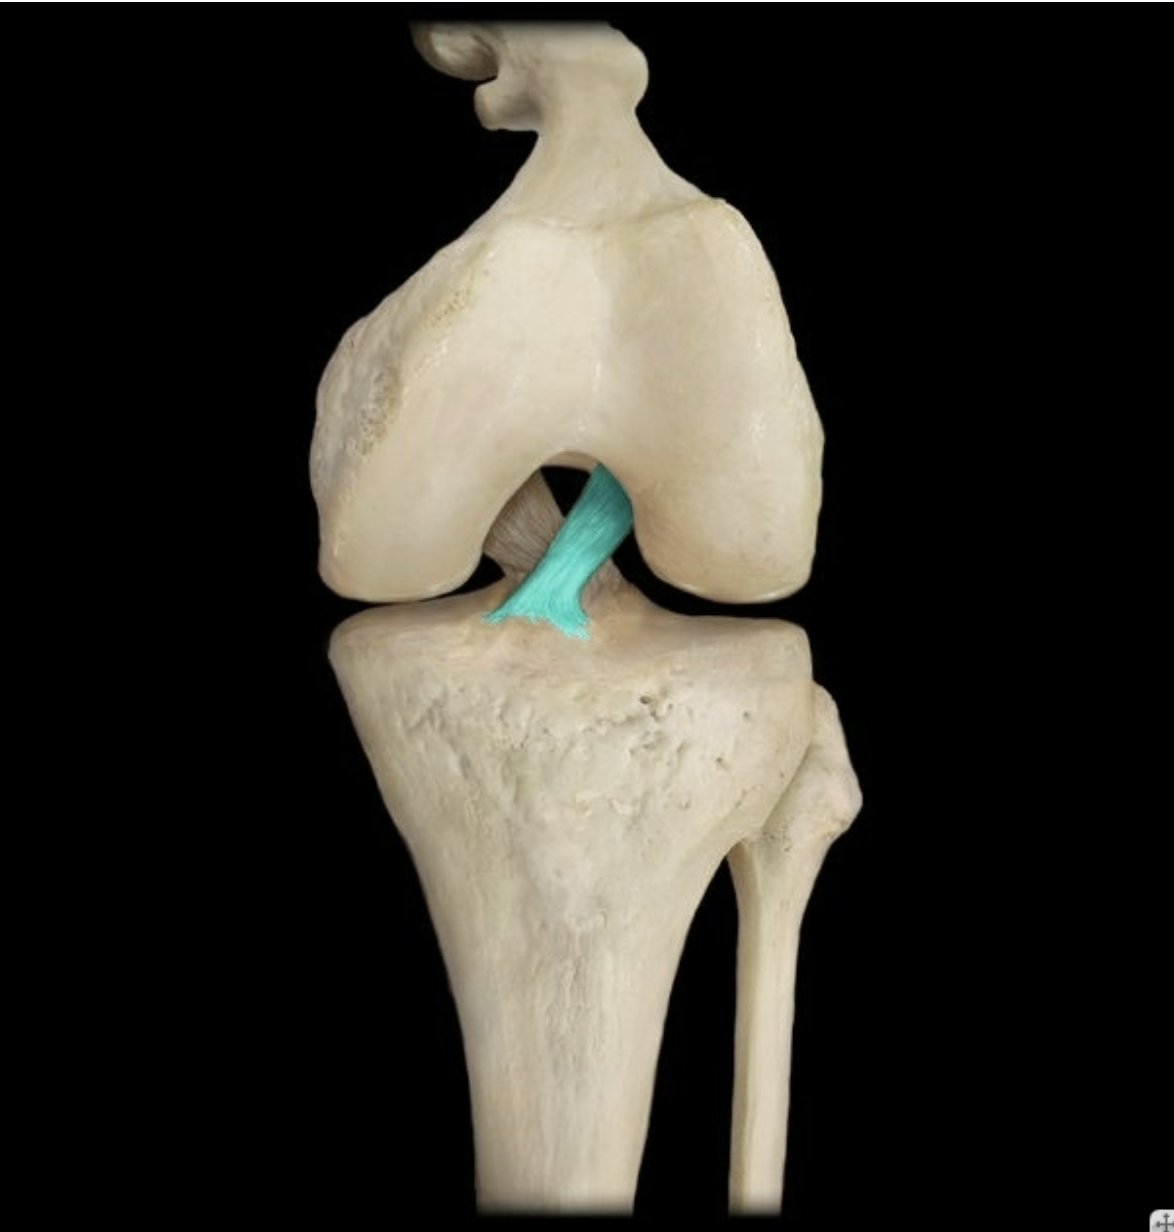

Anterior cruciate ligament

Posterior cruciate ligament